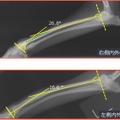

3Dプリンタモデル活用で犬の難手術に成功……変形矯正の整形手術で大幅な時間短縮 2枚目の写真・画像

藤井動物病院と整形外科専門獣医師グループのONE for Animalsは8日、犬の特殊な整形外科症例を、3Dプリンタモデルを使い術前計画と模擬手術を行うことで、手術の時間短縮に成功したことを発表した。